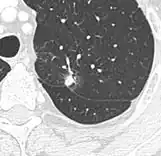

- Margin morphology: a spiculated margin is a risk factor for cancer.[8] Benign causes tend to have a well defined border, whereas lobulated lesions or those with an irregular margin extending into the neighbouring tissue tend to be malignant.[10] In particular, spiculations are highly predictive of malignancy with a positive predictive value up to 90%.[9] Also, a "notch sign", which is an abrupt indentation of the nodule, increases the risk of cancer, but may also be found in granulomatous diseases.[9]

-

subpleural nodule.[9] -

Round well-delineated solid lung nodule with smooth border.[9] -

Lobulated nodule.[9] -

Spiculated lung nodule.[9] -

A "notch sign".[9] -

A triangular perifissural node can be diagnosed as a benign lymph node.[9]